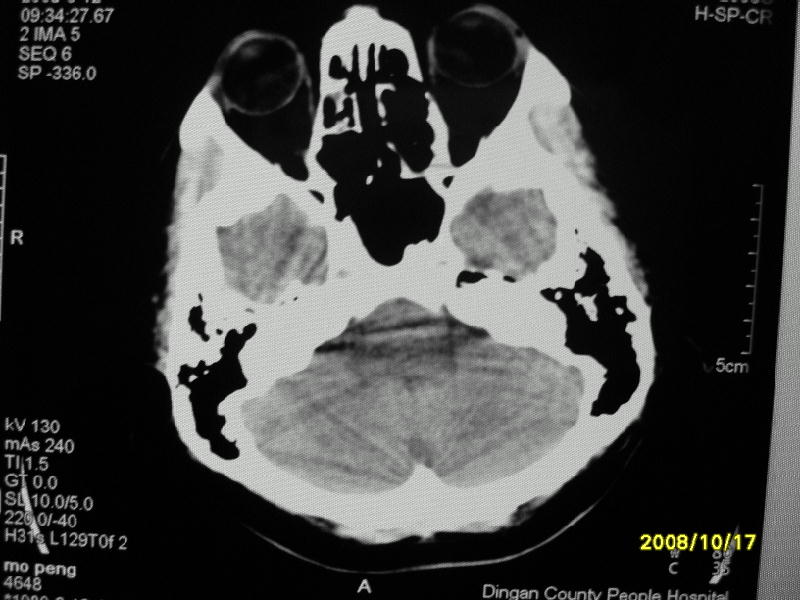

检查名称:     ct颅脑平扫           男     28岁

表现:左顶叶见斑点状致密影。边缘清,大小约0。3*1。0cm,余脑实质密度及灰白质结构示见异常。脑室系统大小,形态,密度未见异常。脑沟。脑裂。脑池未见异常密度影。中线结构无移位。

印象:左顶叶少许钙化灶

左顶叶见斑点状致密影。边缘清,大小约0。3*1。0cm,余脑实质密度及灰白质结构示见异常。脑室系统大小,形态,密度未见异常。脑沟。脑裂。脑池未见异常密度影。中线结构无移位。

印象:左顶叶少许钙化灶。

镰旁钙化

脑沟钙化,考虑陈旧性炎症后

考虑脑膜钙化或脑膜血管钙化

镰旁钙化或顶骨内板骨嵴部分容积效应,建议mri矢状位扫描观察与顶骨的关系。排外后者。

左顶叶见斑点状致密影